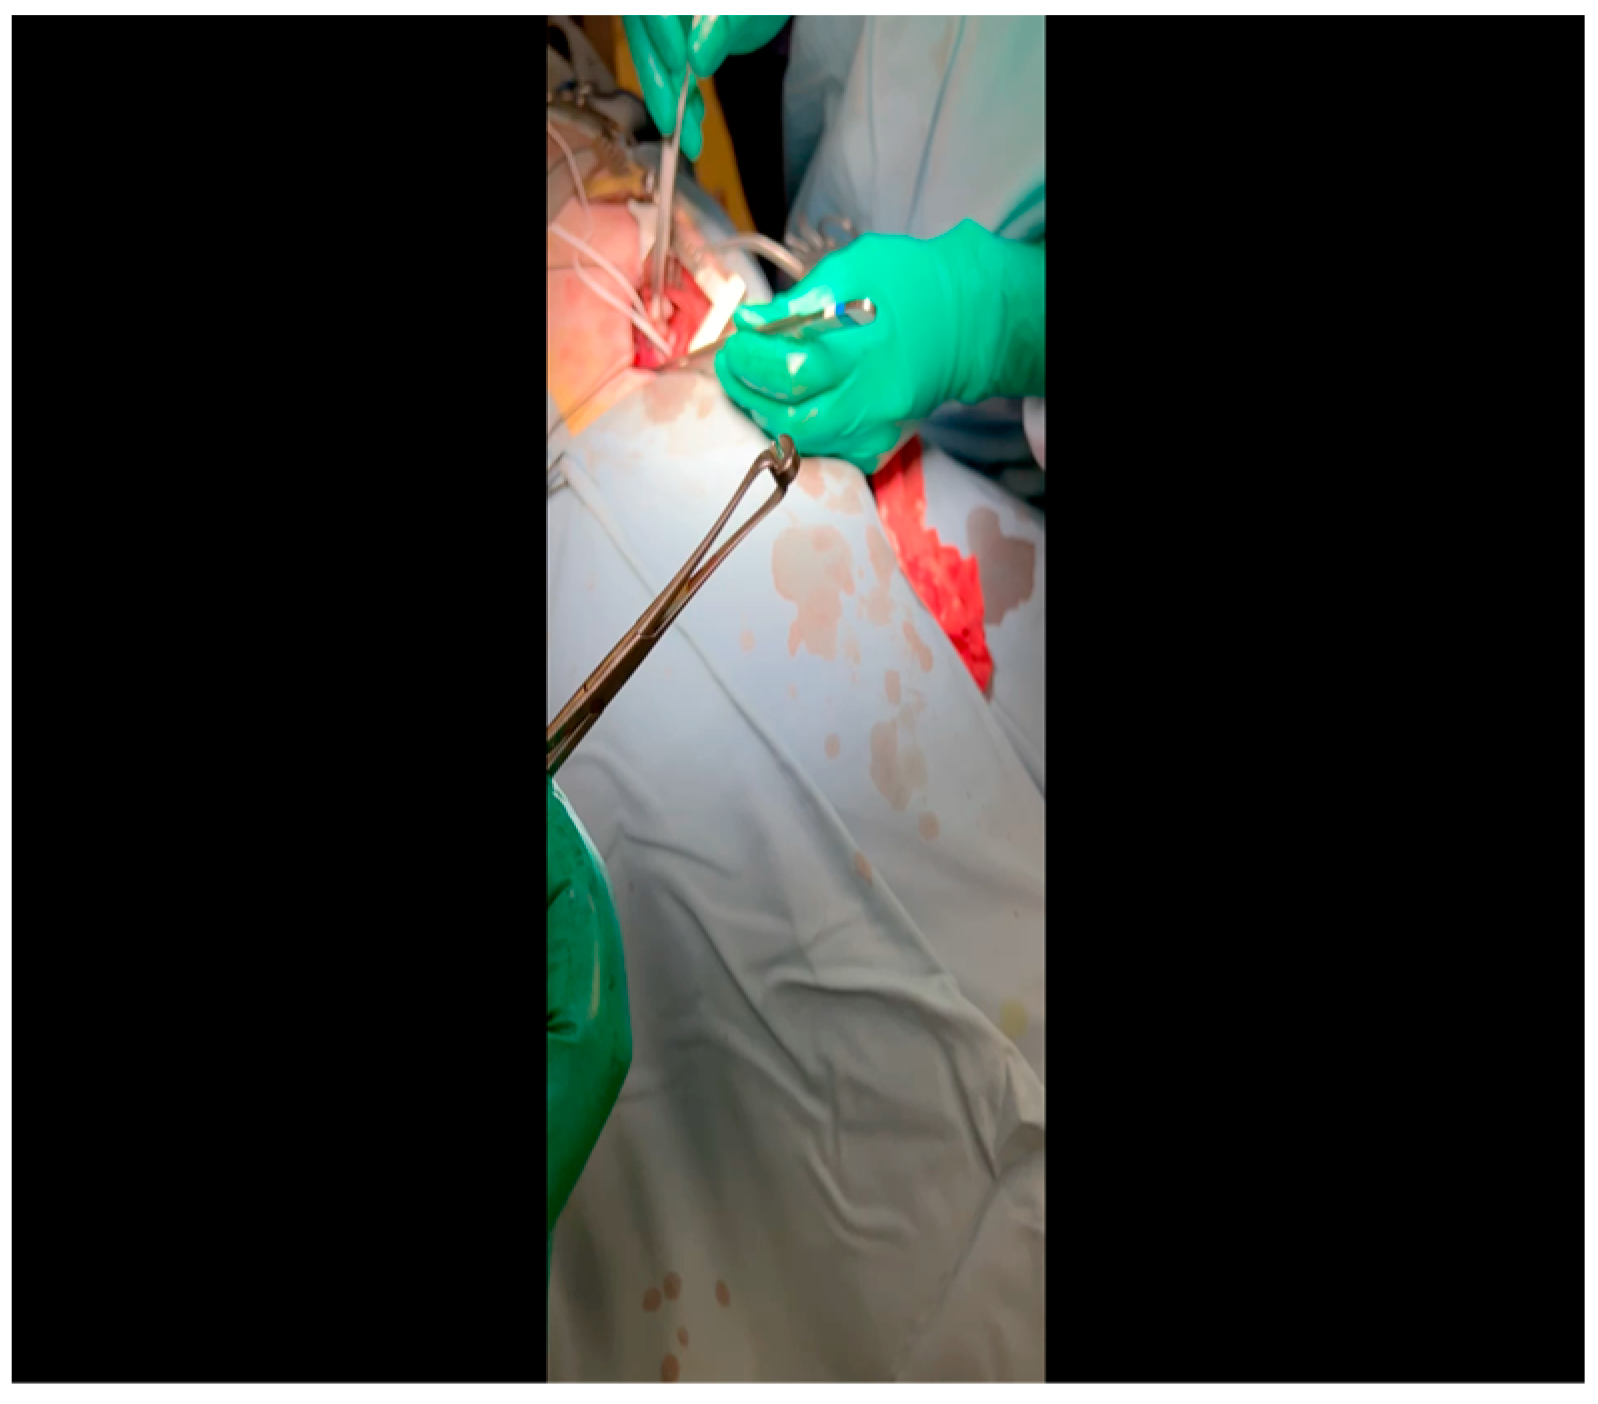

- A mini left thoracotomy is then performed: a transverse incision is made along the ribs beginning at the left sternal border and extending laterally for approximately 6 cm. This incision is placed just inferiorly to the left axillary fold (Figure 1).